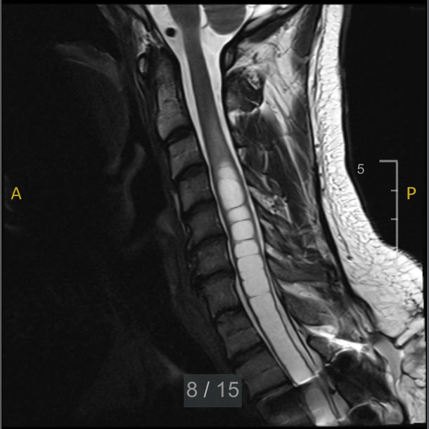

Diagnosis of syrinx is guaranteed through MRI. Using an instrument such as MRI, healthcare professionals can assess the size, location (cervical syrinx, thoracic syrinx, or other), and associated abnormalities, such as Chiari malformation or spinal cord tethering. Once detected, MRI is used serially to document progression.